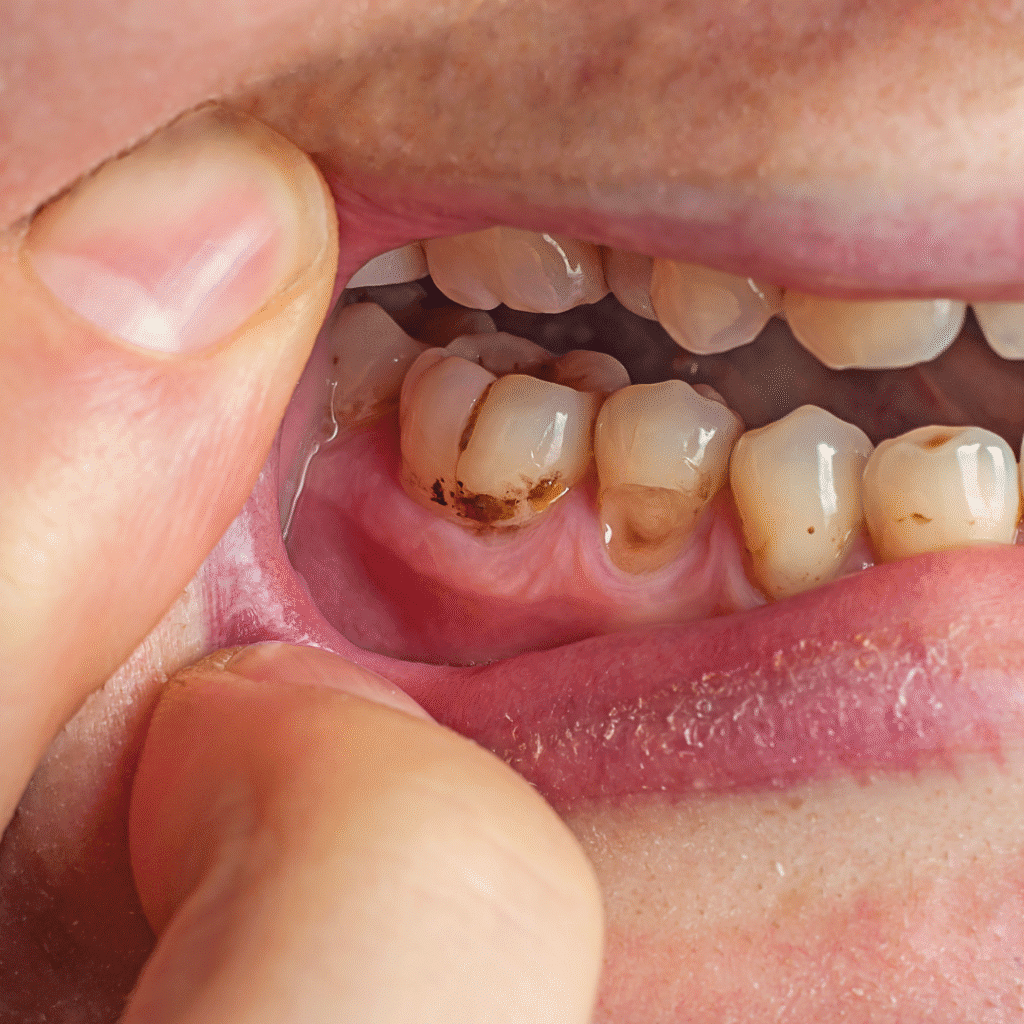

• White or brown spots on the enamel

If decay progresses, you may experience visible holes, persistent toothache, or swelling near the gum line.